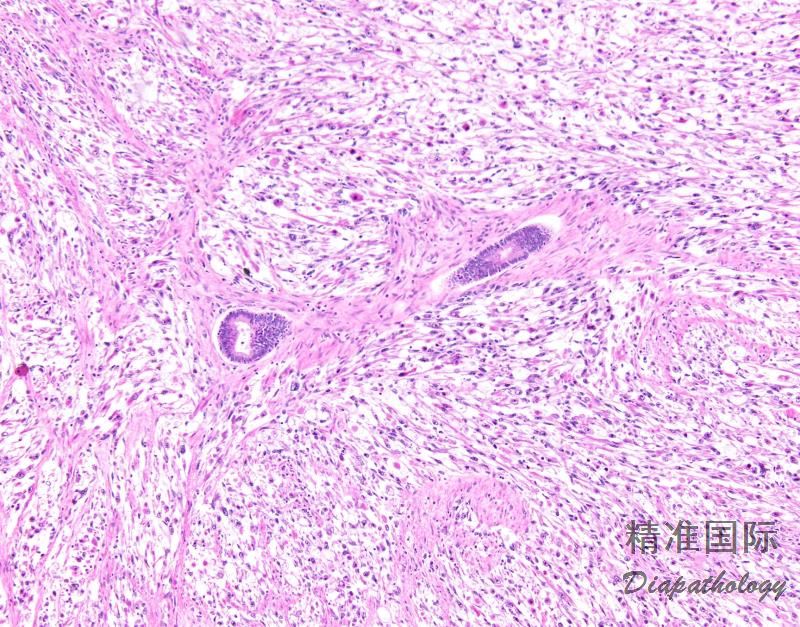

肿瘤内遍布管状腺体和裂隙样腔隙,衬覆上皮的乳头状间质由表面突入囊腔,导致叶状肿瘤样外观;

腺体周围间质细胞丰富是腺肉瘤的特征性表现,几乎每个病例都可见细胞丰富的袖套样间质围绕腺体或在表面上皮下方形成富于细胞的间质条带,至少局部如此;

间叶细胞的核异型性程度不一,在多数肿瘤中为轻到中度异型性,核分裂像通常为 2 ~ 4 个/10HPF,或者更多;如具备其他指征没有核分裂也可诊断